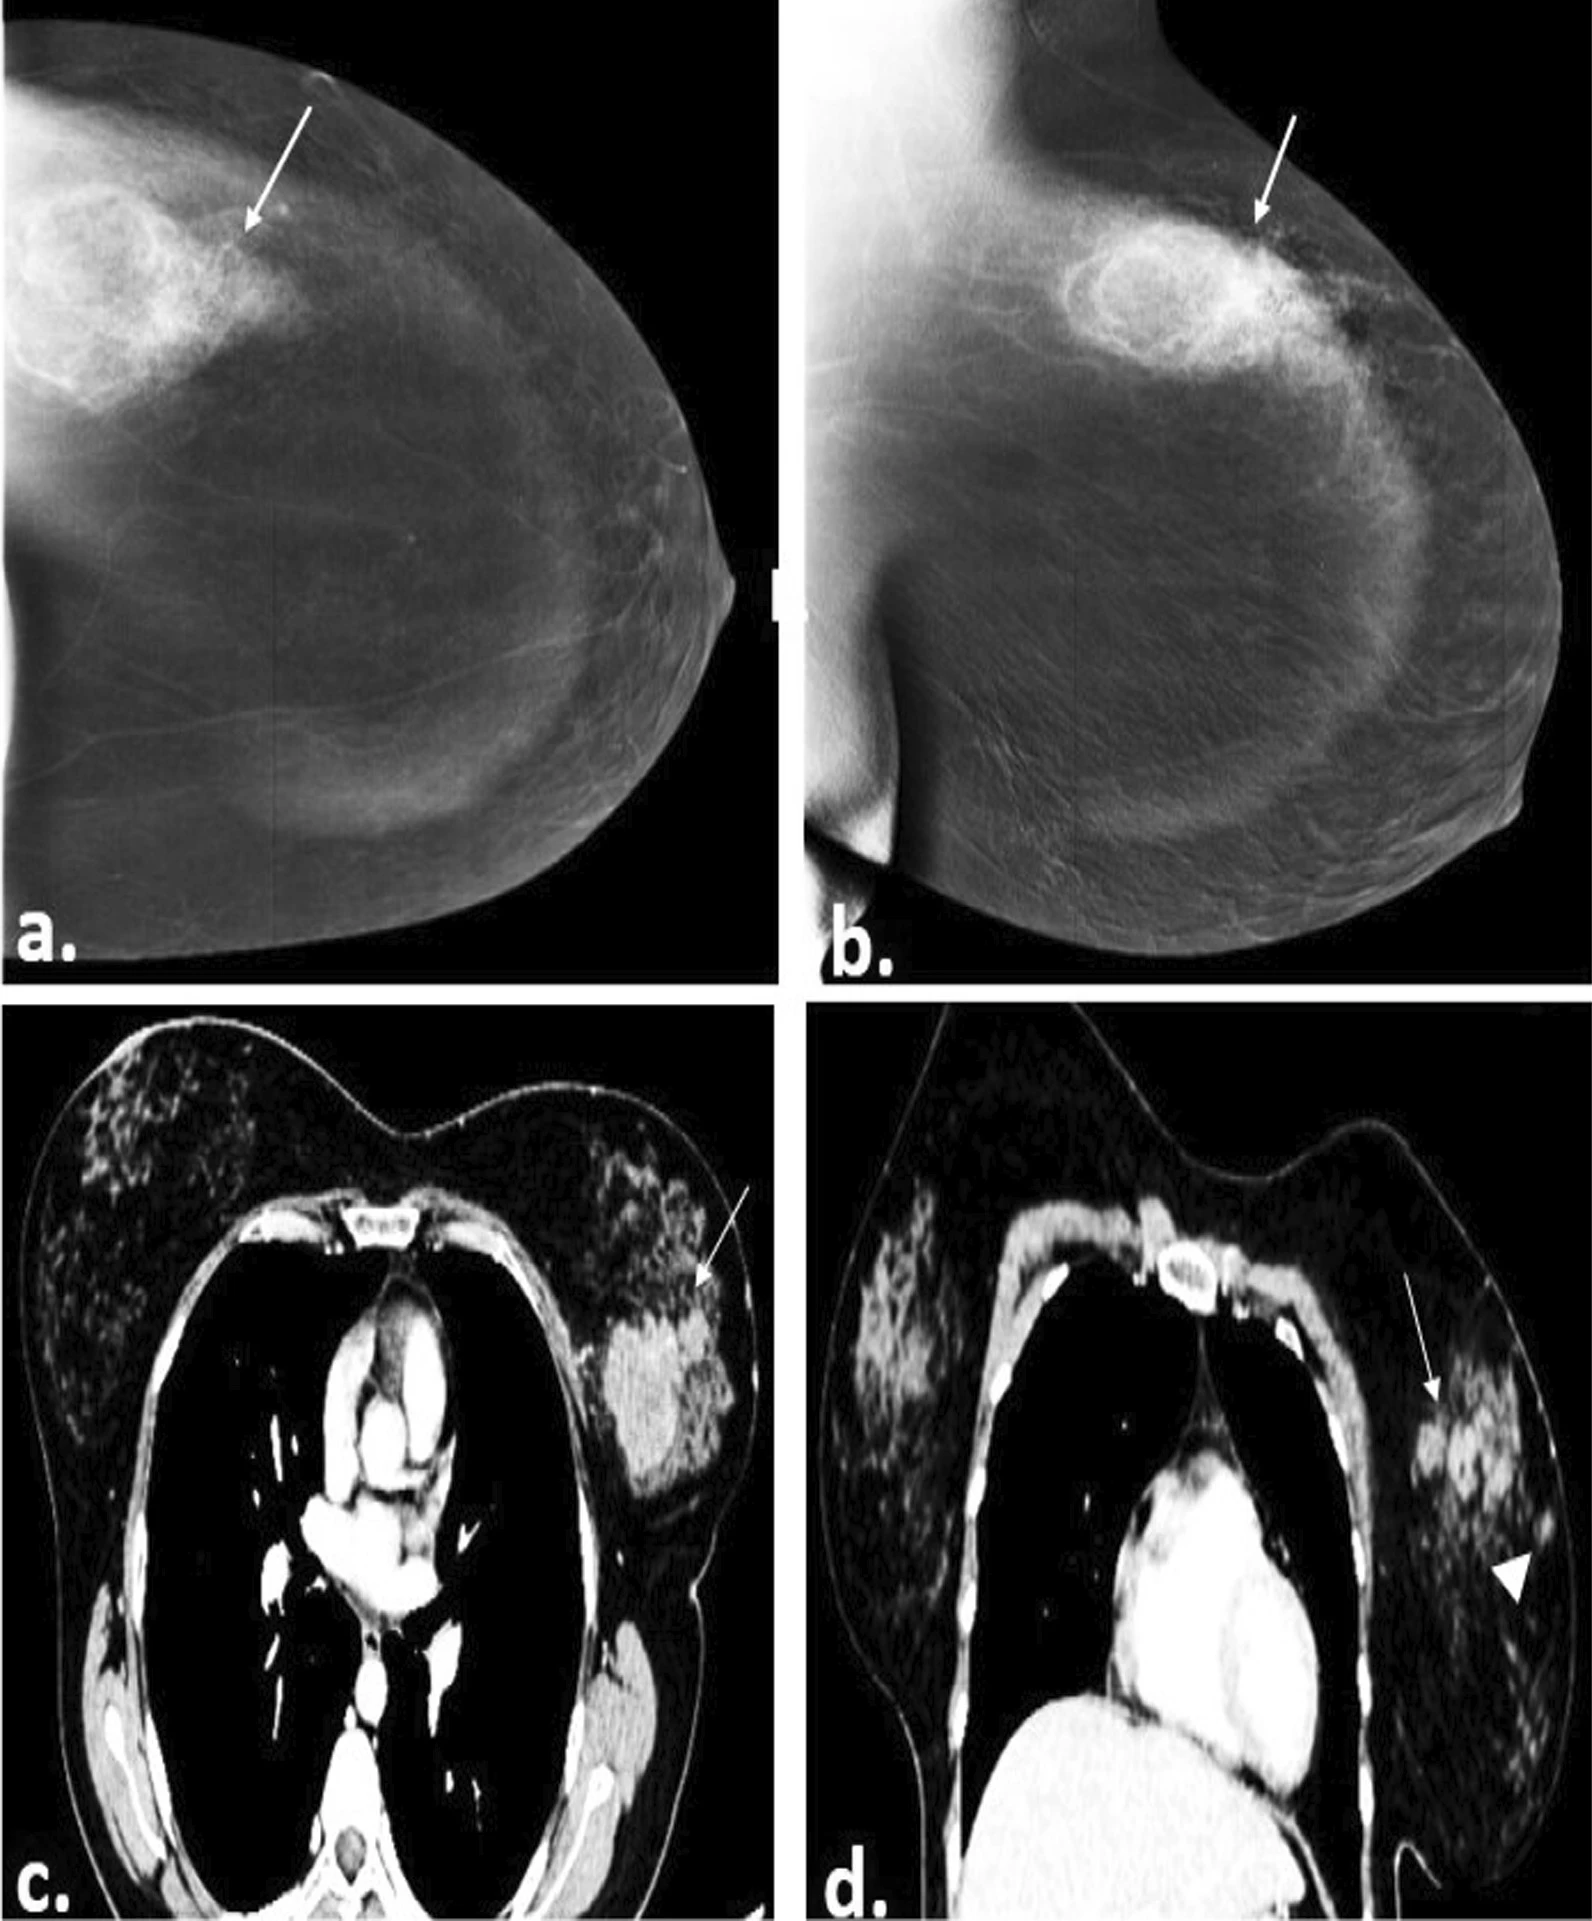

CT scans, or computed tomography, are a non-invasive method for diagnosing breast cancer using X-rays. Unlike standard X-rays, CT scans produce cross-sectional, multi-dimensional images from various angles. These images are combined to create a comprehensive view of the breast tissue from all sides. The process involves a person lying down while X-rays pass through the body, with detectors measuring variations in light intensity across the tissue. A computer then processes this data into 3D images, enabling radiologists to identify abnormalities, such as white dots indicating tumor activity (Figure 3). In cases where distinguishing between benign and malignant tumors is challenging, contrast-enhanced CT scans or ionizing agents may be used to improve clarity.

Figure 3: Image of a 40-year-old female patient’s right breast with CESM (contrast-enhanced mammography) (a, b) and contrast-enhanced CT chest (c, d) showing multiple spiculated heterogeneously enhancing masses (straight arrows). The histopathology result was Invasive Ductile Carcinoma grade II21.